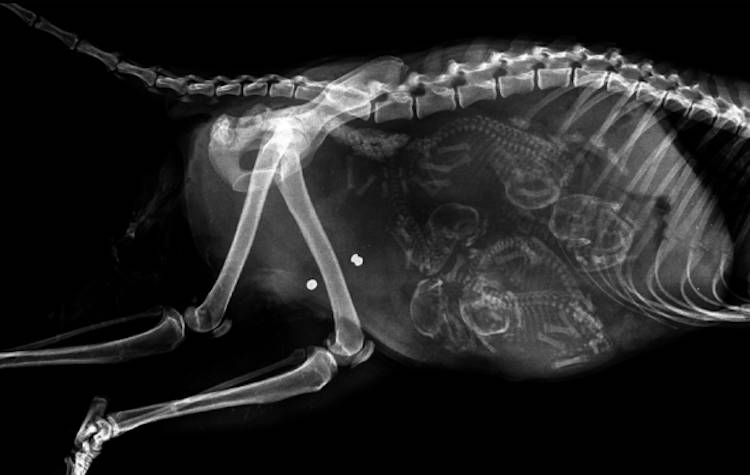

怀孕的猫,在怀孕后约45天,小猫的骨骼就会生长得能够用 X 光拍摄到。